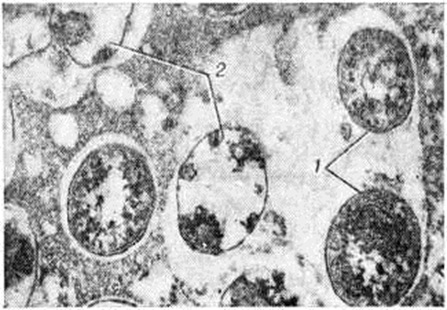

Электронно-микроскопическими исследованиями установлено, что ультраструктура возбудителя Лепра принципиально не отличается от строения других видов грамположительных бактерий. На поверхности микобактерий Лепра выявляется равномерный электроннопроницаемый (осмиофобный) слой толщиной 5—10 нанометров (наружный диффузный слой клеточной стенки). За ним следует осмиофильный слой клеточной стенки толщиной от 3 до 10 нанометров, состоящий из двух очень тонких некоторое, плотно прилегающих друг к другу. Непосредственно к внутренней поверхности клеточной стенки примыкает наружный слой цитоплазматической мембраны (рисунок 1), представляющей собой, как и у других бактерий, трёхслойную мембрану толщиной 7,5—9 нанометров. В бактериальной клетке встречаются 1—2 мезосомы с выраженным полиморфизмом (петлеобразные, везикулярные, трубчатые, пластинчатые, гроздевидные). В цитоплазме выявляется сравнительно небольшое количество рибосом, сферические электронно-плотные включения волютина диаметром 20—50 нанометров, включения, имеющие вид ограниченных мембраной вакуолей (предположительно липоиды), и гомогенные тельца, природа которых остаётся неизвестной. Ядро не имеет определённой формы, расположено в центре клетки вдоль её длинной оси, не ограничено мембраной. Иногда в лизирующихся под воздействием химиотерапии клетках микобактерий Лепра выявляются спороподобные образования (рисунок 2 и 3).

Рис. 2. | ||